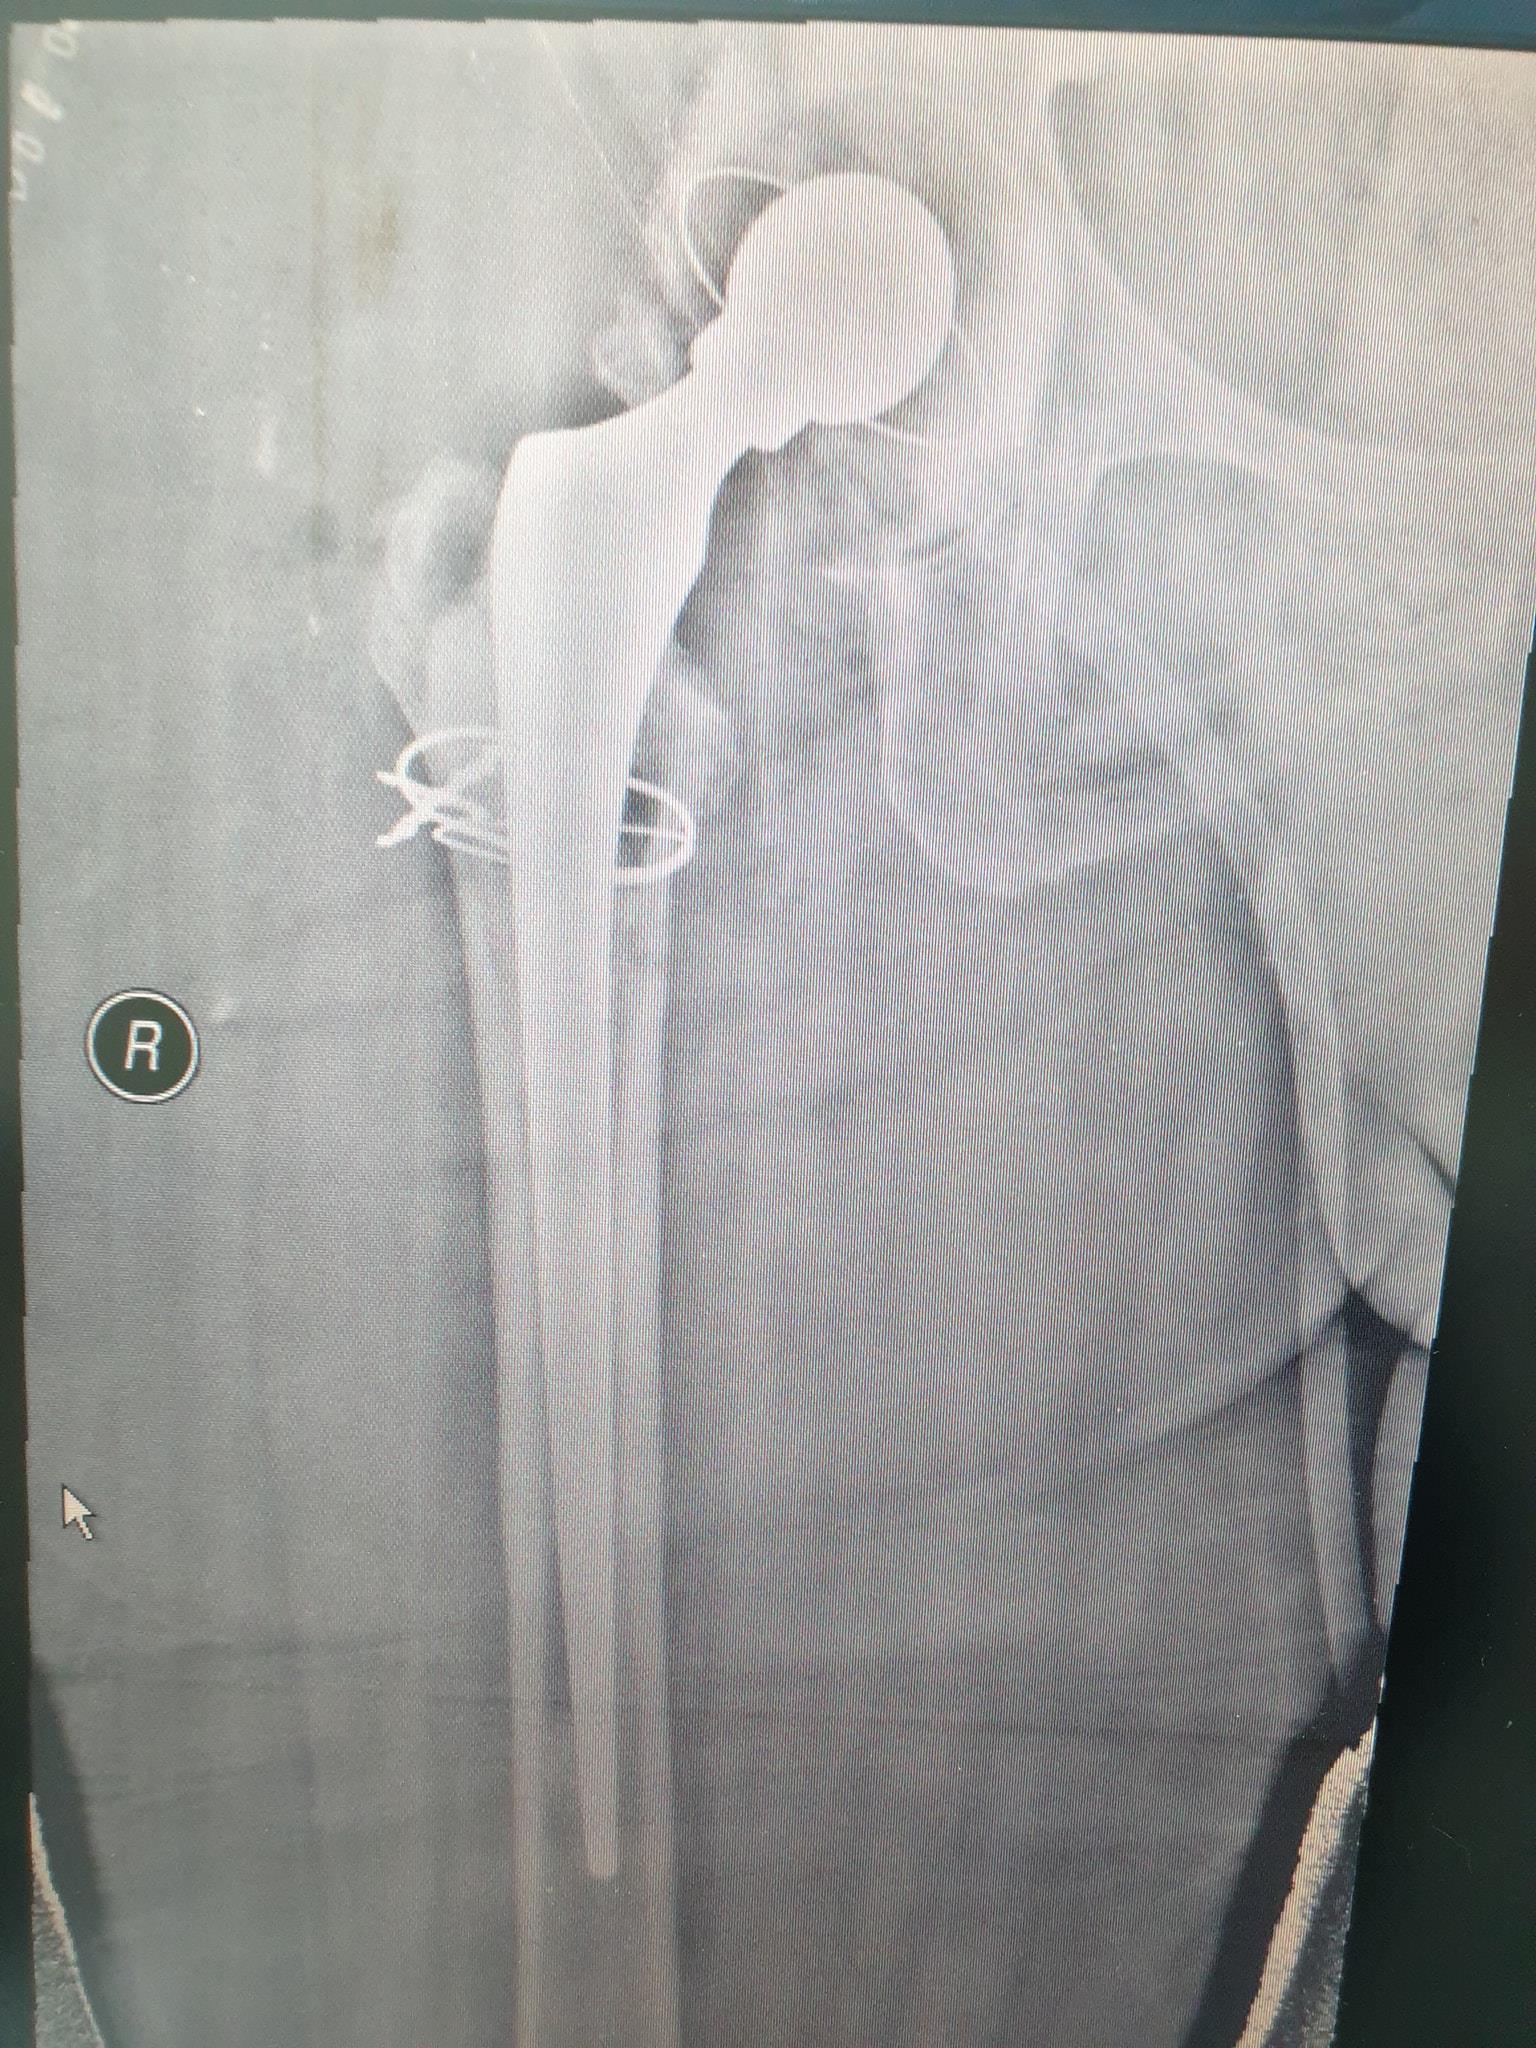

زراعة المفاصل الصناعية ورك و